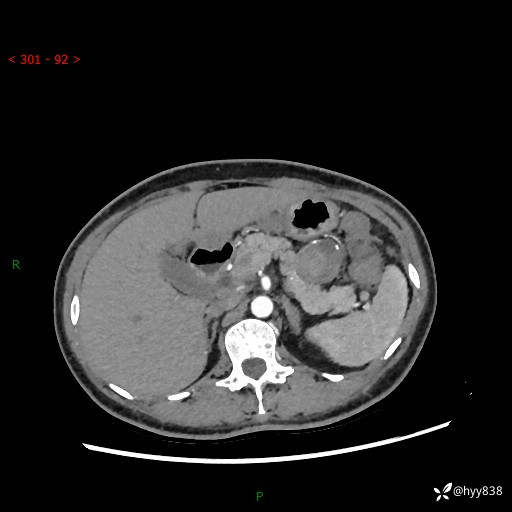

胰腺CT平扫

img